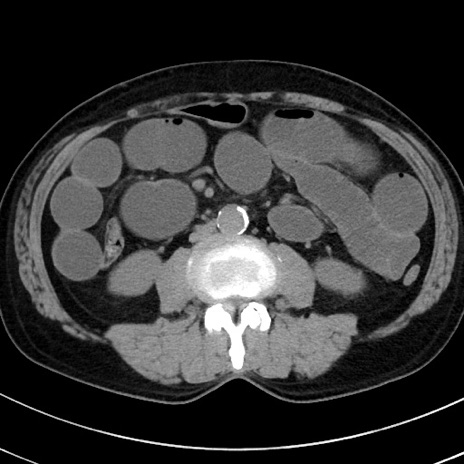

症例38(横断像)

【症例】70歳代 男性

【主訴】腹痛・嘔吐

【現病歴】昨晩より、嘔吐・腹痛あり。今朝になっても嘔吐あり。来院。

【既往歴】心臓バイパス手術、開腹胆摘、腸閉塞

【身体所見】BP 107/71mmHg、HR 116/min、腹部:平坦、軟、下腹部に軽度圧痛あり。反跳痛なし。

【データ】WBC 15100、CRP 0.32